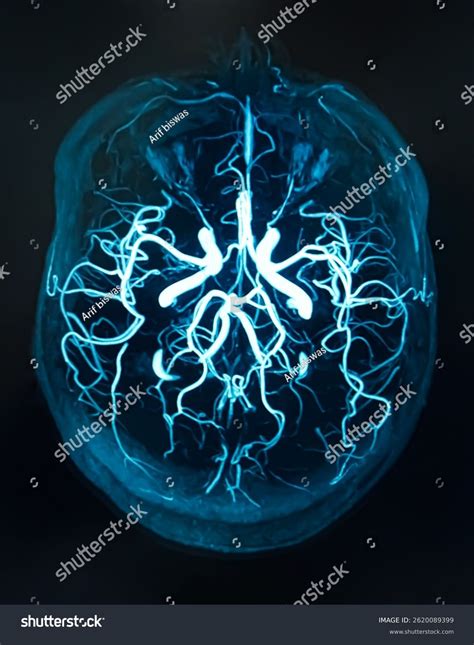

Magnetic Resonance Venography (MRV) is a sophisticated medical imaging technique that uses magnetic fields and radio waves to generate detailed images of the cerebral veins. Unlike a standard MRI, which primarily looks at the brain tissue itself, an MRV is specifically designed to assess blood flow and identify potential abnormalities within the venous system.

The imaging machine detects the signals emitted by the blood flow within these enhanced vessels, creating a high-resolution map of the venous drainage system. The entire process is non-invasive, meaning no surgical intervention is required.